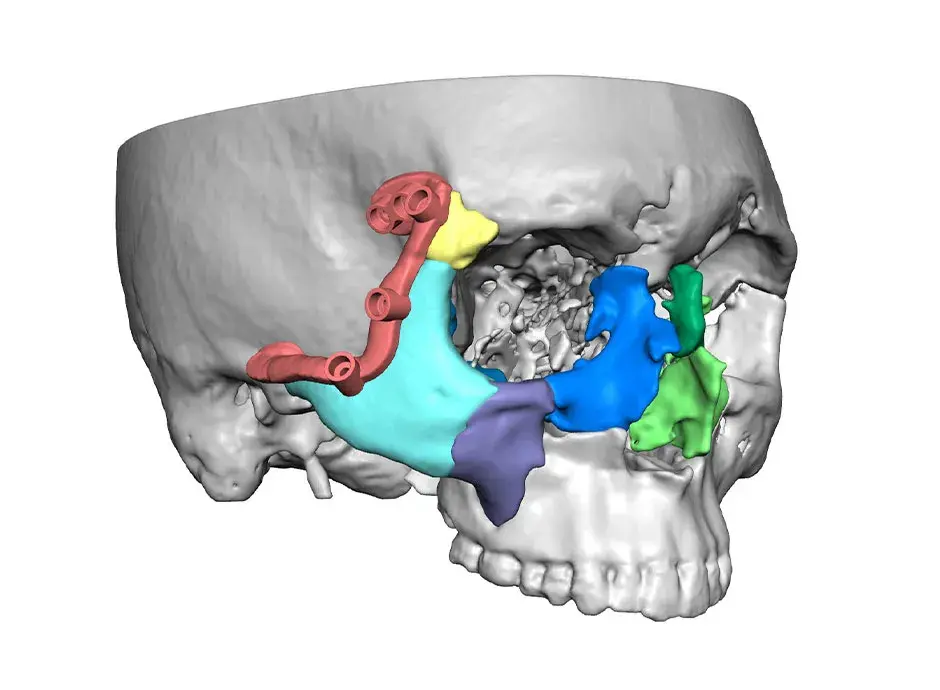

3D Systems' VSP® surgical planning solutions for craniomaxillofacial (CMF) applications received FDA clearance as a service-based approach to personalized surgery over 10 years ago.

3D Systems and Stryker Corporation have partnered to provide surgeons with best-in-class products and services for craniomaxillofacial surgeries. As a leader in personalized healthcare solutions, 3D Systems has planned and delivered devices for more than 140,000 patient-specific cases. The Stryker Craniomaxillofacial business specializes in providing patient-specific options and innovative solutions that help drive efficiencies in surgical suites. The combination of Stryker’s specialized team and advanced implants with 3D Systems' cutting-edge 3D printing technologies and expert consulting services positions both companies to provide a superior level of service to healthcare professionals who use these revolutionary solutions.